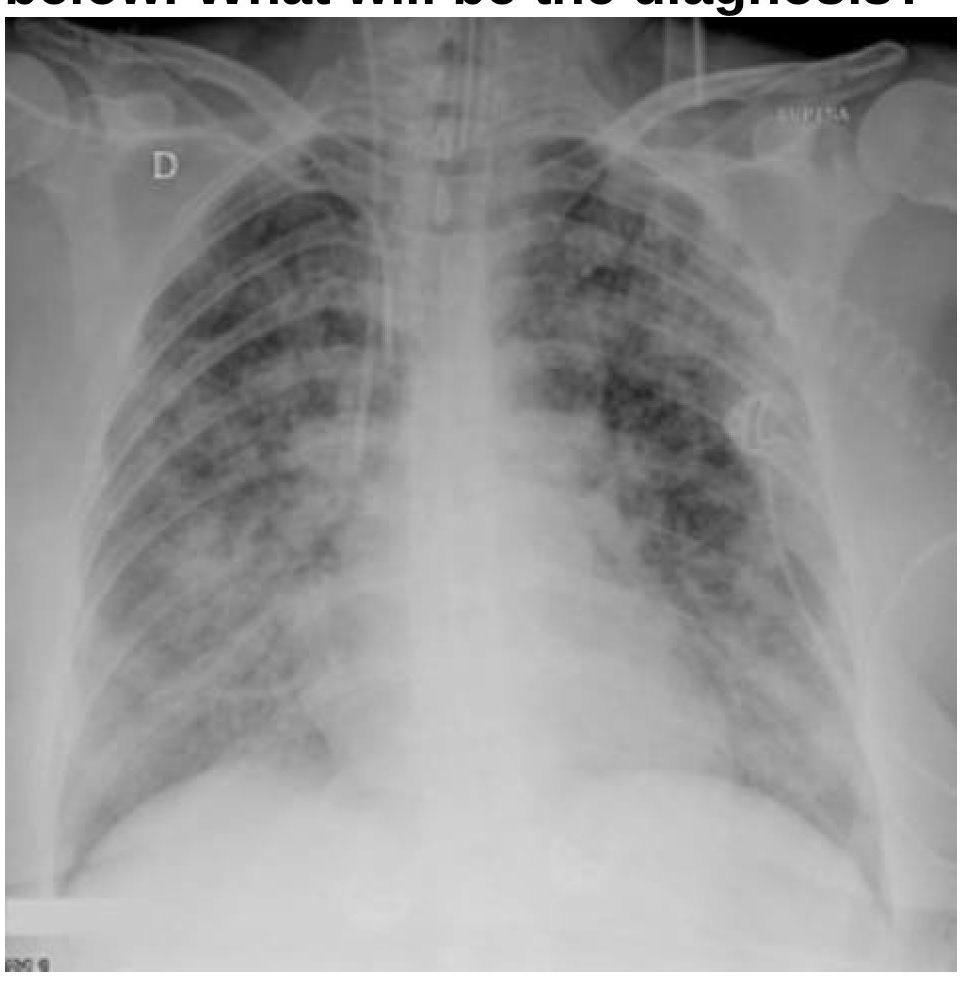

A patient with a known case of acute pancreatitis develops breathlessness and bilateral basal crepitations on day 4. What is the most likely diagnosis based on the chest radiography image?

Explanation: ***Acute Respiratory Distress Syndrome (ARDS)*** - The chest radiograph shows **bilateral patchy infiltrates** and **diffuse alveolar opacities** consistent with ARDS, especially in the context of **acute pancreatitis** as a known risk factor. - The development of **breathlessness** and **bilateral basal crepitations** (rales) on day 4 further supports ARDS due to fluid accumulation in the lungs. *Bilateral pneumonia* - While pneumonia can cause bilateral infiltrates, the **symmetrical and widespread distribution** seen on this radiograph, combined with the context of acute pancreatitis, makes ARDS a more likely diagnosis. - Pneumonia typically presents with fever, productive cough, and lung consolidation, which are not specifically highlighted as primary symptoms over the breathlessness. *Carcinogenic Pulmonary Embolism* - Pulmonary embolism typically manifests with **sudden onset dyspnea**, pleuritic chest pain, and sometimes hemoptysis, and chest X-rays are often normal or show subtle findings like a **Westermark sign** or Hampton's hump. - The widespread bilateral infiltrates seen in the image are **not characteristic of pulmonary embolism**. *Lung collapse (atelectasis)* - Atelectasis usually appears as a ** localised area of increased opacification**, often with volume loss (e.g., tracheal deviation, elevated hemidiaphragm), and is often unilateral or segmental. - The **diffuse, bilateral, and often fluffy infiltrates** seen in this image are not consistent with typical atelectasis.